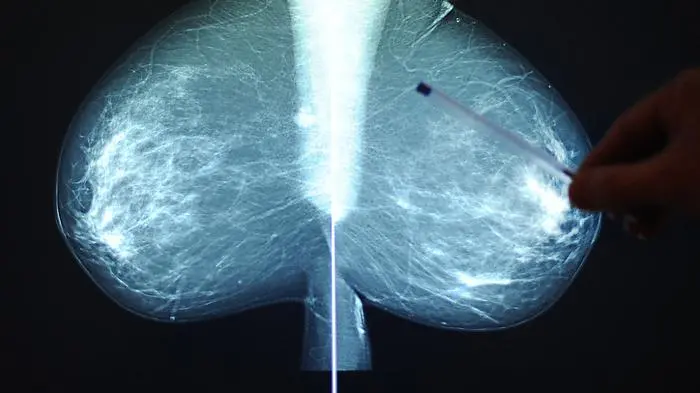

Brustkrebs bei früher Diagnose immer besser behandelbar

Jede achte Frau in Österreich erkrankt im Lauf ihres Lebens an Brustkrebs. Das bedeutet rund 5.600 Neudiagnosen pro Jahr. Je früher der Krebs erkannt wird, desto besser ist die Fünf-Jahres-Überlebensrate, erläuterte Marija Balic vom LKH/Universitätsklinikum Graz am Mittwoch bei einer Pressekonferenz des Pharmaunternehmens Gilead in Wien. Dort wurde anlässlich des Brustkrebs-Monats Oktober an die Wichtigkeit der Früherkennungsuntersuchung und der Selbstkontrolle erinnert.